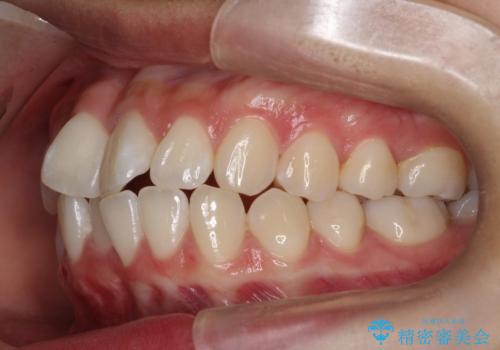

前歯のがたがたを綺麗にしたい

- 前歯がねじれていること、出ていることを主訴に来院されました。

前歯の突出感も改善され、満足していただきました。